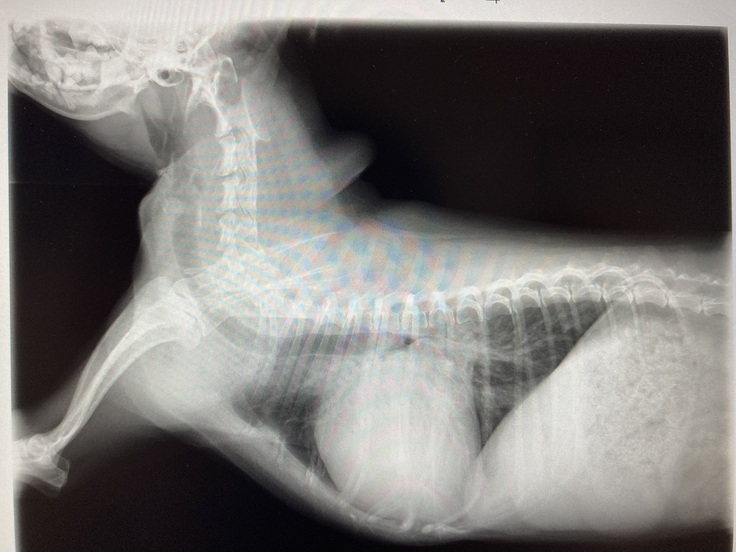

▼現在のココのレントゲンとエコー写真

心臓が大きく肥大していて

逆流も多く、かなり悪い状態で

余命6〜9ヶ月と宣告されました。